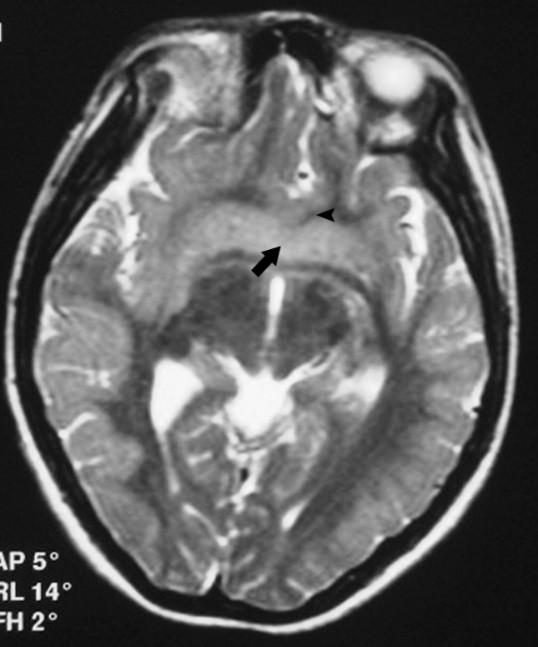

Blunted anterior Corpus, with subtle fusion at the level of the anterior commissure…?

Fusion (lack of cleavage) is just anterior /superior to the anterior commissure.

Ectopic posterior pituitary “bright spot.” Missing infundibular stalk.

Contrast or ultra thin T2 needed to confirm.